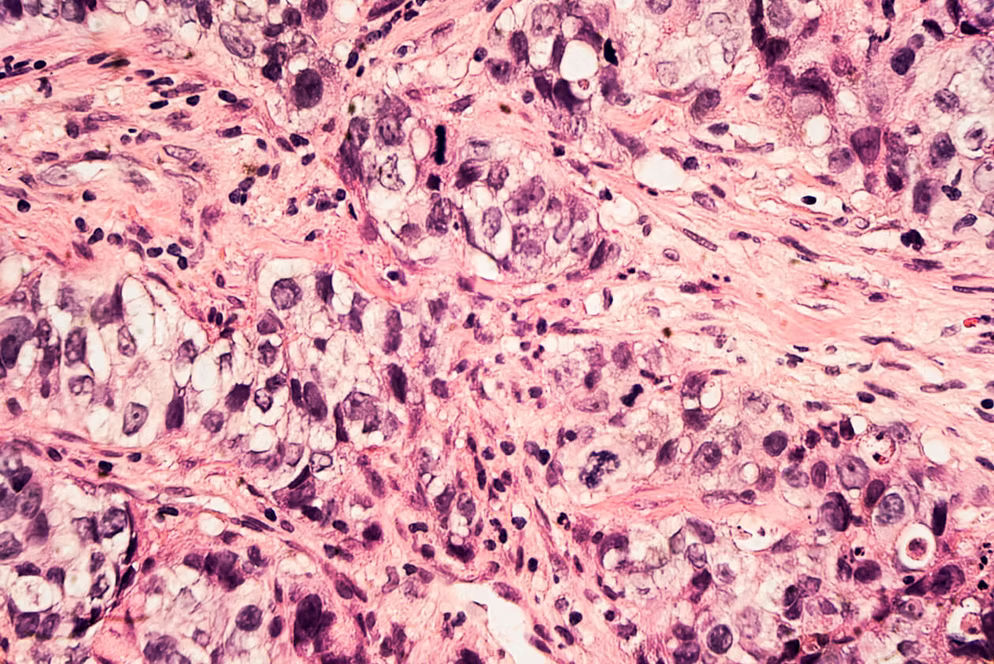

• Radiologen und Pathologen

⚙️ FORTSCHRITTLICHE DIAGNOSTISCHE TECHNOLOGIEN

Unsere Partnerkrankenhäuser verwenden die neuesten bildgebenden Verfahren und Biopsiesysteme, um eine präzise und frühzeitige Diagnose zu gewährleisten: